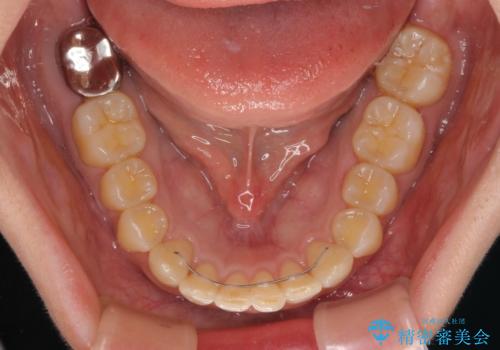

インビザライン単体で対応ることも検討できますが、達成する可能性が低いため、カリエールディスタライザーという補助装置を併用して、より確実性を上げることとしました。

奥歯の咬み合わせと深い咬み合わせを改善した後、インビザラインで歯列を整えることとしました。

カリエールディスタライザーや部分的なワイヤー矯正を併用したことで、確実かつ短期間で治療を終えることができました。